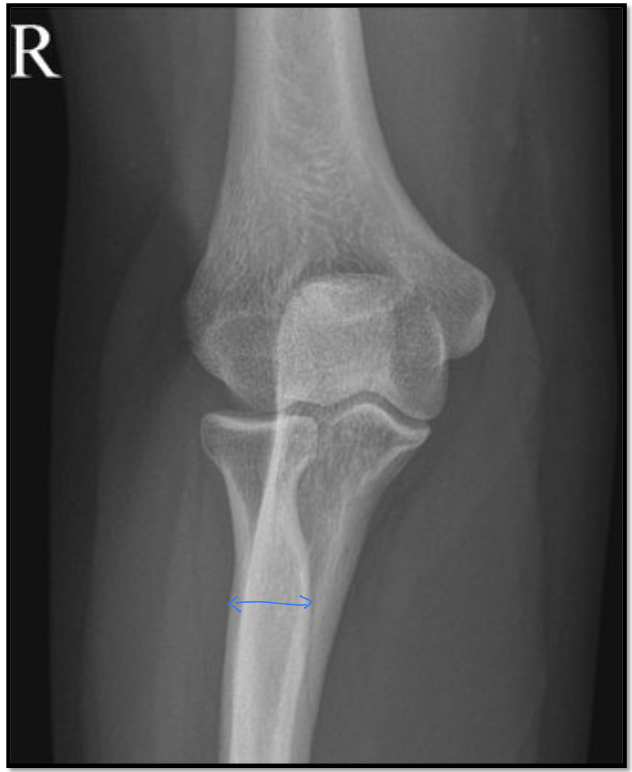

9

AP elbow criteria

A

Medial and lateral humeral epicondyles

are in profile

* 1/4” overlap of radial head on ulna

* 50% of the radius at the radial

tuberosity is superimposed by the ulna

* Capitulum-radial joint space is open

↳have all 3 jointson same plane

* Radius and ulna are parallel

10

What is the positioning fault?

How would you fix it?

Too much overlap with the radius and ulna - elbow slightly internally rotated